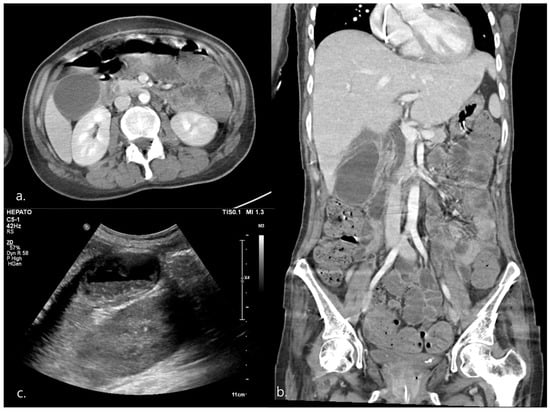

| 1 | HD 65 | 1 | Epigastric discomfort RLQ tenderness Murphy’s sign * | Fever * Elevated CRP *, WBC * | CT, US | 93 × 41 * | 3.76 | (+) * | (−) | Definite AC |